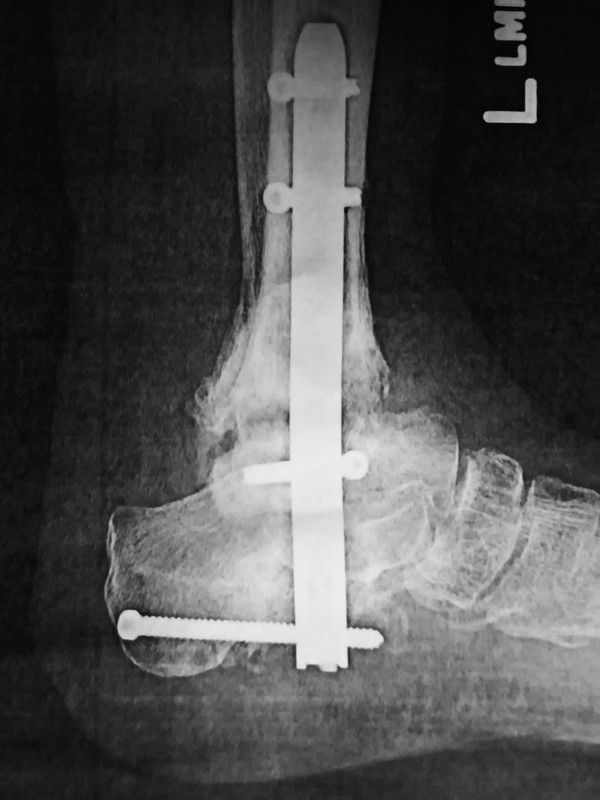

FINALLY got a copy of fusion x-ray. Doc says although it looks good, still unsure of ultimate outcome. So take it easy for now.

got until the end of year to have the im nail removed. been averaging 9  on vas scale painwise. like the irs its quite taxing. and thhen theres a front coming through early this weekend. :technical: btw danke jim :)